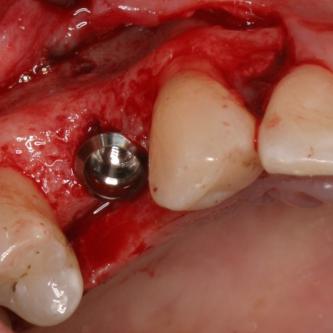

Exemple 11: Pendant l'implantation on remarque un manque d'os sur la partie externe, les spires de l'implant sont visibles.

Exemple 11: Une greffe d'os est effectuée afin de compenser l'épaisseur d'os manquante.

Exemple 11: Le tout est recouvert d'une membrane collagène.

Exemple 11: Après cicatrisation environ 6 mois, le moignon est vissé sur l'implant.

Exemple 11: La couronne céramique en place.